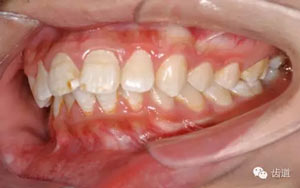

3.重要錯(cuò)位:

如個(gè)別牙的唇(頰)舌向錯(cuò)位、擁擠反合、鎖合等。

1)、牙齒的擁擠度:牙冠寬度的總和與牙弓現(xiàn)有弧形的長(zhǎng)度之差即為擁擠度。一般分為3度。

75.jpg

Ⅰ度:間隙差距為2-4mm.

Ⅱ度:間隙差距為4-8mm.

Ⅲ度:間隙差距為8mm以上.